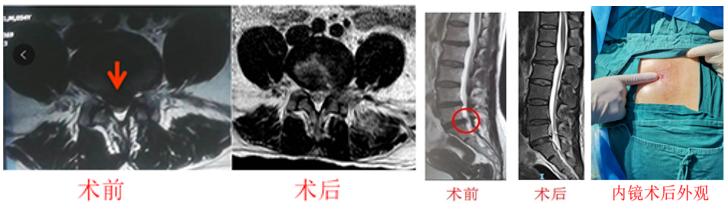

2. 经皮内镜下腰椎椎管减压术是治疗腰椎间盘突出症、腰椎管狭窄症的安全、有效的微创术式,经过江晓兵教授的改良优化后,手术可高效、安全完成,效果优于开放手术、显微镜或显微内窥镜下腰椎间盘切除术,而且非常微创,术后当天或1天即可出院、切口只需要7毫米左右、术后1周内即可恢复工作。目前,已能够全面覆盖各种严重椎管狭窄及骨性压迫的腰椎病,部分腰椎滑脱也能够通过内镜来治疗。

真正诠释了我们的宗旨:能孔镜不融合!